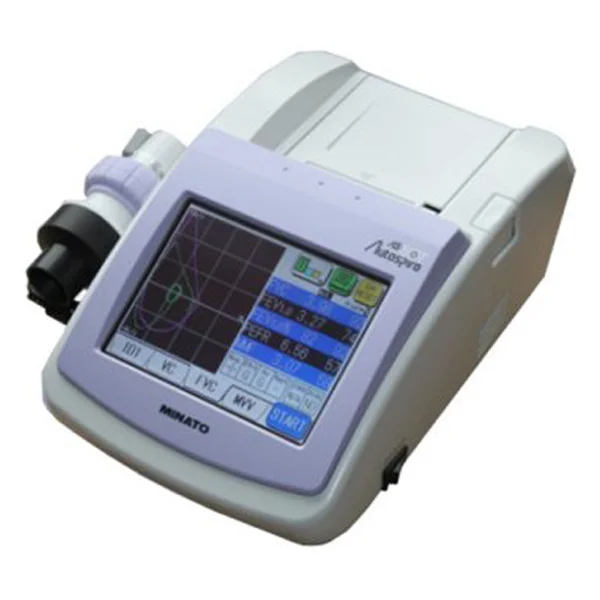

中山高榮電子科技有限公司是一家集自主研制,生產(chǎn)和銷(xiāo)售一體的高新技術(shù)醫(yī)療器械生產(chǎn)企業(yè),嚴(yán)格按照CFDA認(rèn)證,遵守國(guó)家醫(yī)療器械法規(guī)建立了完善的質(zhì)量管理體系,確保提供給客戶(hù)的醫(yī)療器械產(chǎn)品安全健康。公司擁有十萬(wàn)級(jí)、萬(wàn)級(jí)潔凈生產(chǎn)車(chē)間,環(huán)氧乙烷滅菌車(chē)間,有專(zhuān)門(mén)的物理實(shí)驗(yàn)室、理化實(shí)驗(yàn)室和微生物實(shí)驗(yàn)室以及醫(yī)電研發(fā)室、醫(yī)電生產(chǎn)車(chē)間。主要產(chǎn)品有:“太陽(yáng)松”品牌:一次性使用呼吸過(guò)濾器,一次性肺功能儀用過(guò)濾器,咬嘴;“凱華”品牌:醫(yī)用電子產(chǎn)品,肺功能檢查儀等,其中過(guò)濾器,咬嘴可匹配市場(chǎng)上各種不同品牌型號(hào)的肺功能儀使用,可以降低患者吸入或呼出顆粒性物質(zhì)的數(shù)量,防止污染儀器,大限度保障每位受測(cè)者健康安全.